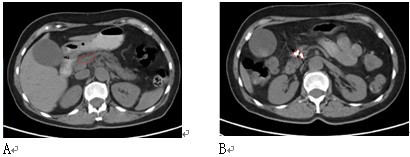

图4 女性,61岁。胰腺颈部3X3cm病变,活检显示腺癌。肝内有3个转移灶(图中未显示)。A:治疗前;B:冷冻加125碘粒子植入治疗,7个月后复查,胰腺和肝内无明显癌肿证据(肝内病变未显示)。患者迄今已生存4年。

图5 女性,64岁。胰腺头部肿块,活检显示鳞癌。给予冷冻加碘粒子植入。A:治疗前;B:治疗后8个月复查。患者生存14个月。